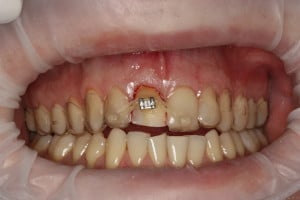

Ekstruzja ortodontyczna – wydłużenie korony klinicznej zęba. Jest ruchem wymuszonym przez siły ortodontyczne a skierowanym do płaszczyzny zwarcia, powodującym rozciąganie włókien ozębnej stymulującym jednocześnie przebudowę wyrostka zębodołowego, co daje zwiększoną objętość kości i dziąsła. Ekstruzja ortodontyczna to skuteczna metoda ratowania zębów po złamaniach koronowo-korzeniowych zębów stałych.

Głównym celem jest uratowanie zęba przed usunięciem. To metoda z wyboru w trudnych przypadkach złamań korzeni zębów przebiegających poniżej przyczepu dziąsłowego. Drugą z metod alternatywnych jest periodontologiczne-mikrochirurgiczne wydłużenie korony klinicznej.

Polecana dla uszkodzonych zębów przedniego odcinka szczęki i żuchwy uszkodzonych wskutek urazu, zmienionych próchnicowo na wysokości szyjki zęba lub resorpcji zewnętrznej tej okolice. Metoda daje szansę na utrzymanie własnego zęba w jamie ustnej bez konieczności zastąpienie go implantem lub mostem.

Przykład ekstruzji ortodontycznej za pomocą płytki termoformowalnej i zameczka ortodontycznego: